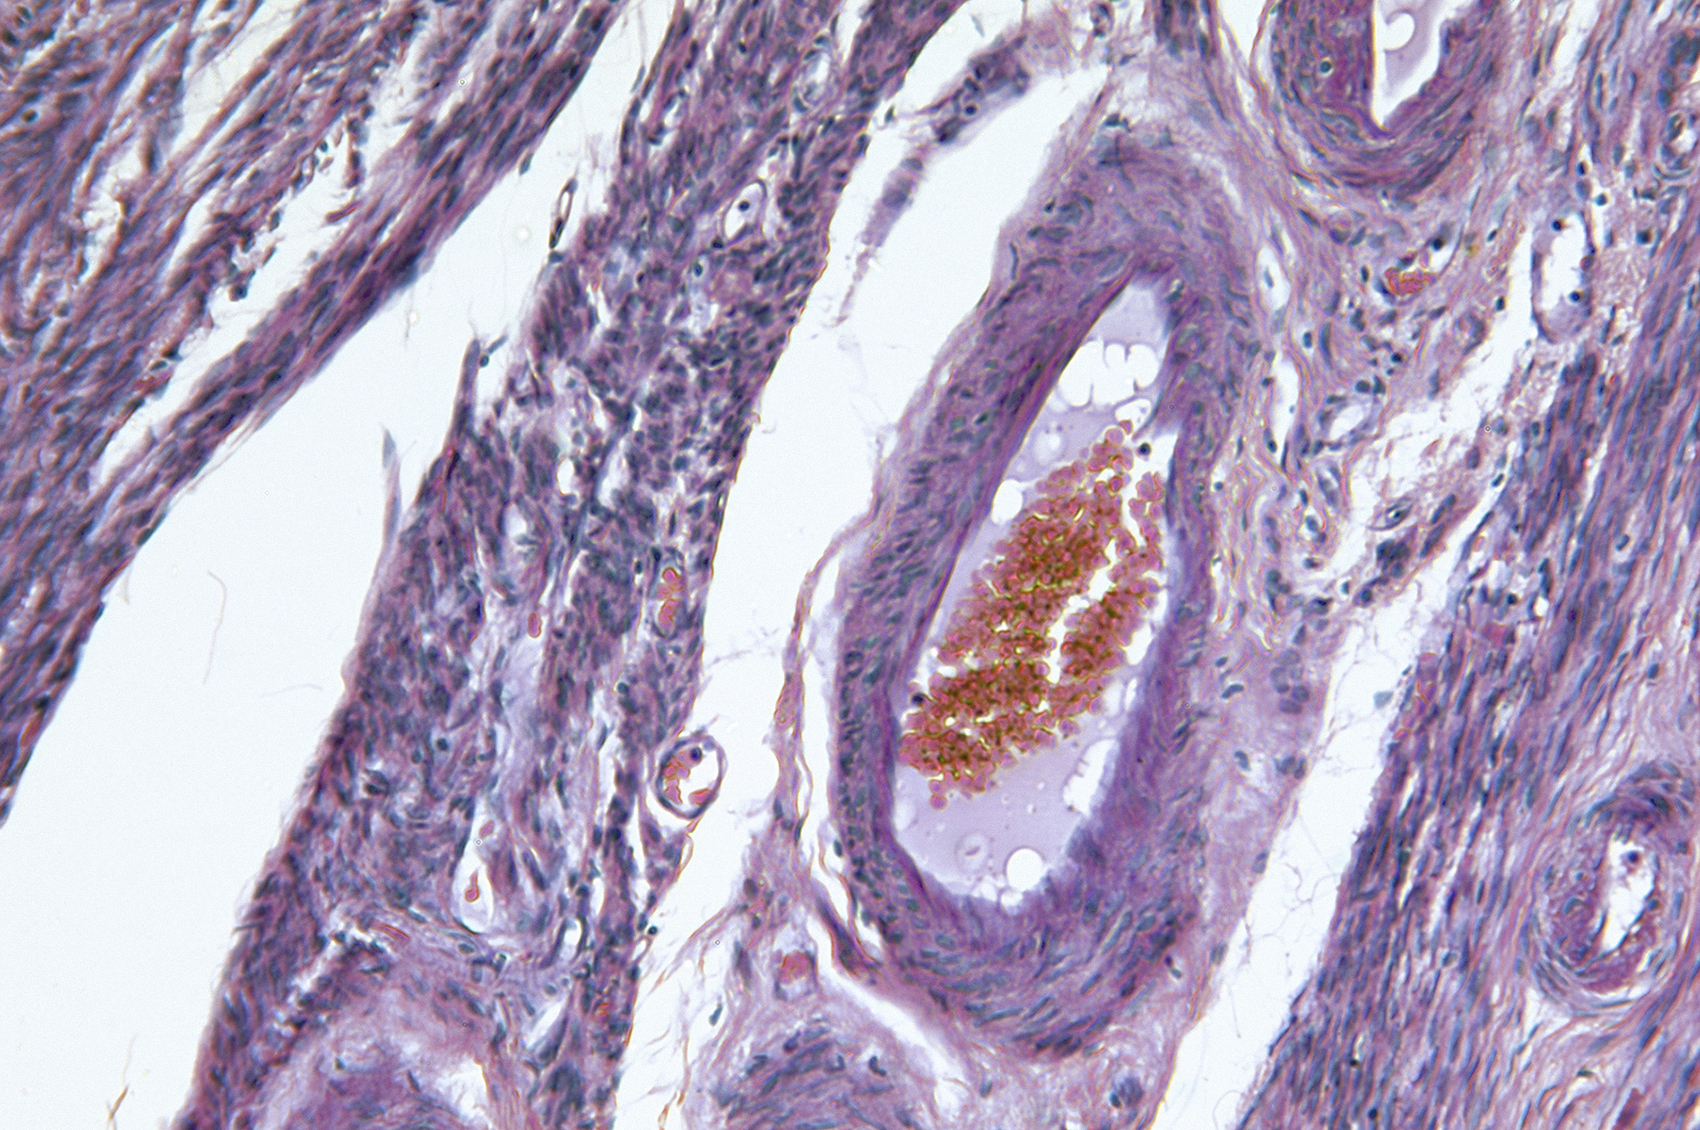

Patientinnen mit primärem fortgeschrittenem oder rezidivierendem Endometriumkarzinom weisen vor allem im Langzeitverlauf unter dem Behandlungs­management mit Carboplatin plus Paclitaxel eine schlechte Prognose auf. Diese kann mit Hilfe einer kombinierten Immuntherapie deutlich verbessert werden. Wir sprachen mit PD Dr. med. Marcus Vetter, Chefarzt am Tumor­zentrum Baselland, über die Diagnostik und Therapie des Endometriumkarzinoms sowie seine Erfahrungen mit Dostarlimab in der klinischen Praxis.